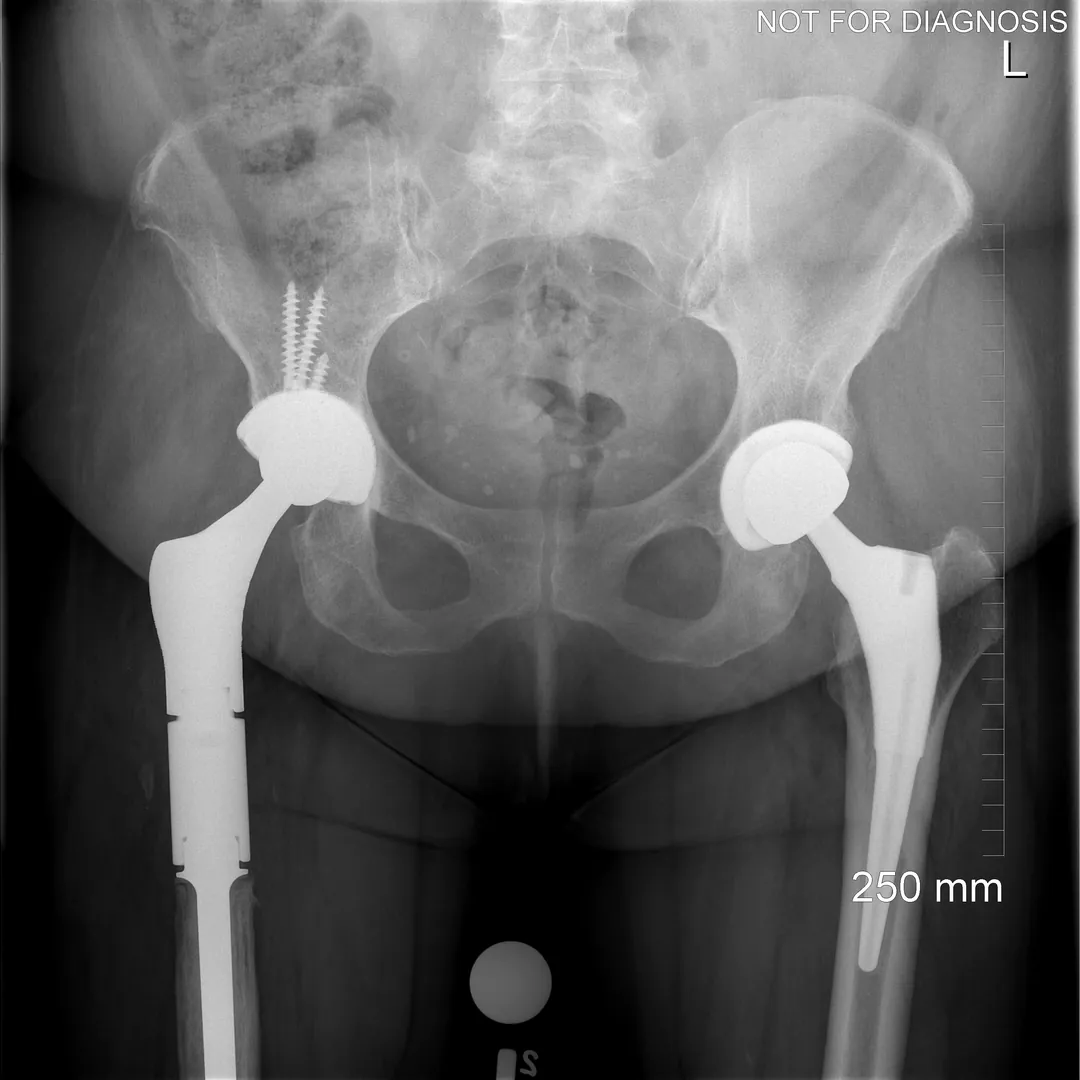

Hip Resurfacing vs. Total Hip Replacement (THA)

Hip Resurfacing

- Preserves more natural bone (the femoral head is capped rather than replaced)

- Uses a larger ball size, which may reduce the risk of dislocation

- If needed, it can usually be revised to a total hip replacement

Total Hip Replacement (THA)

- Removes the femoral head and replaces it with a stem and ball

- Replaces the socket with a cup and liner (many bearing options exist)

- Suitable for a wider range of patients, including those with more advanced arthritis

- Excellent pain relief and predictable outcomes for most patients